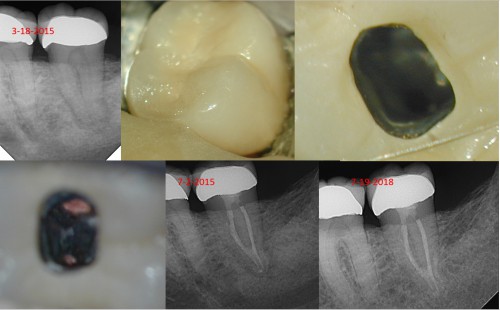

Amalgam restorations

Recent completes: Case 1: Previously initiated, the RD could not locate negotiate/locate the canals. I […]